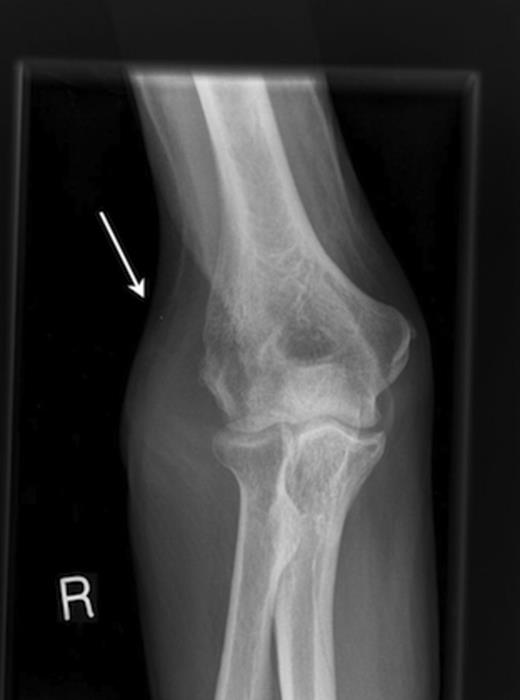

A chest radiograph demonstrated consolidation in the right lower zone. X-ray of the right great toe (Fig. 2) showed destruction of the distal phalanx with adjacent soft tissue swelling, and of the right elbow showed soft tissue swelling over the lateral aspect with possible cortical destruction of the lateral epicondyle (Fig. 3).

Radiograph of right elbow demonstrating a soft tissue swelling over the lateral epicondyle.